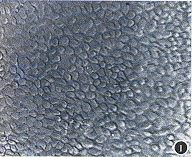

1.细胞培养:组织块接种后细胞很快呈膜状扩展生长,约10天达生长饱和,细胞大小一致,呈多角形,角膜缘和角膜中央上皮细胞的形态相同,仅后者细胞略大(图1,2)。不同的是角膜中央上皮细胞在传第1代后细胞基本停止生长,细胞从多角形变为长梭形,不能形成细胞单层(图3);而角膜缘上皮细胞能够保持增殖至第3~5代后才逐渐丧失上皮细胞形态,生长停止(图4)。

图1 角膜缘上皮细胞原代培养第10天 ×100